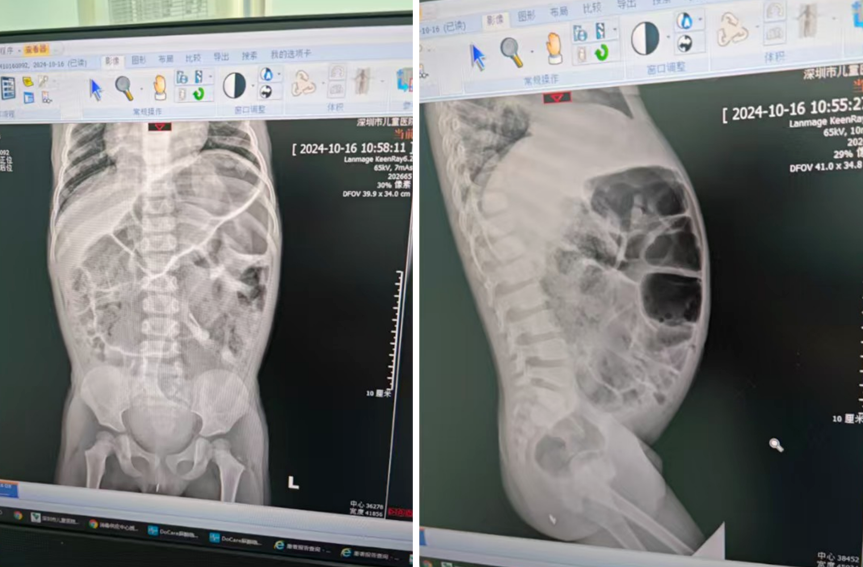

沐沐拖到4岁多才来手术,“憋”出了一个问题:肠子涨成球。

虽然“借”了小鸡鸡做便便出口,但终究是“涓涓细流”,肚子里不可避免地堆积了大量宿便,有一段结肠被撑得涨成了气球,长达9厘米。

第一次手术时,毛建雄和团队不得不把这段肠子拖到肚皮外,在肠子上开个洞,抽出一大堆宿便,又黑又臭。

不过孩子大了,“也有大的好处”,肠子变大了,更好分离。大肠被一层腹膜包裹,第二次手术时,医生得先把它分离出来,才能拖到新造的肛门口。分离的过程必须小心翼翼,稍有不慎就可能误伤膀胱、尿道及周边的神经,造成尿失禁等后遗症。